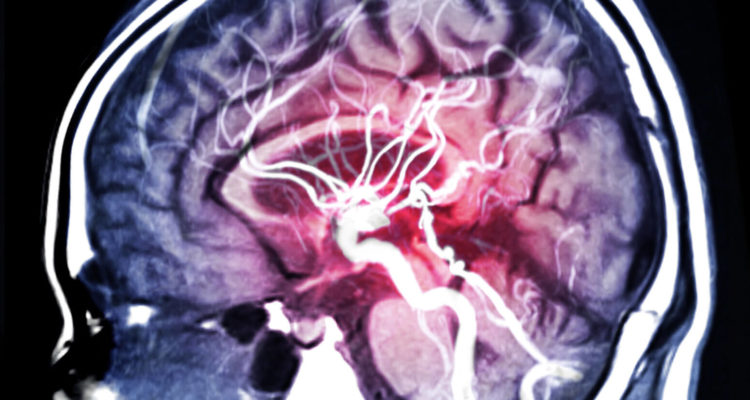

Інсульт виникає, коли мозок не отримує достатньо крові, що позбавляє його кисню і поживних речовин. В результаті клітини мозку відмирають. При цьому дослідження показують, що шанс зіткнутися з інсультом на 80% вище в один і той же час доби.

Так робота Американської кардіологічної асоціації, опублікована в журналі Stroke, показала, що ймовірність інсульту в період між 6 і 12 годинами на 80% вище, ніж в інший час.

“Число інсультів, що реєструються в період з 6 ранку до 12 години дня на 49% вище, що збільшує ризик на 79% в порівнянні з іншими 18 годинами в добі”, – розповідають вчені.